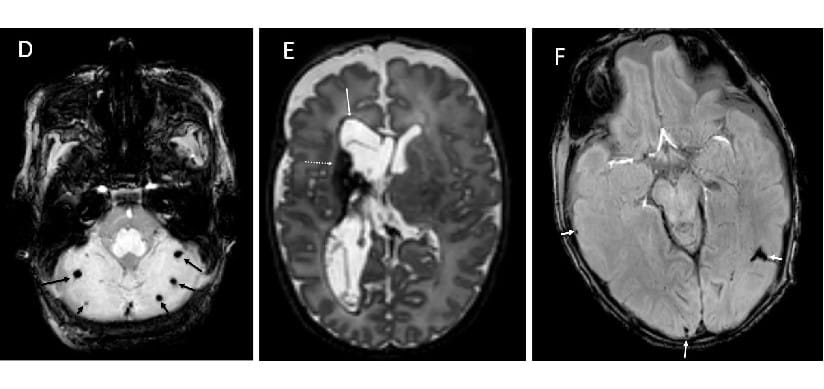

The Parikh Lab employs advanced brain MRI tools such as volumetric, diffusion, and functional MRI for early identification of biomarkers of brain injury/delayed development that are predictive of disabilities in individual high-risk neonates/infants. For example, structural and functional connectivity biomarkers are poised to meet this critical need.

The lab’s current focus is to understand the nature of the commonly encountered diffuse white matter abnormalities and to develop early prognostic models of motor, cognitive, and behavioral abnormalities in a geographic cohort of 350 very preterm infants – The Early Prediction Study. In addition to using multivariable regression modeling, the study is employing newer machine learning/artificial intelligence approaches to uncover novel prognostic biomarkers to enhance outcome prediction of neurodevelopmental disabilities. This important step will facilitate risk stratification/early detection, at birth, to design clinical trials of targeted neuroprotective interventions during the critical window of the first 3 years after birth when brain plasticity is at its peak.